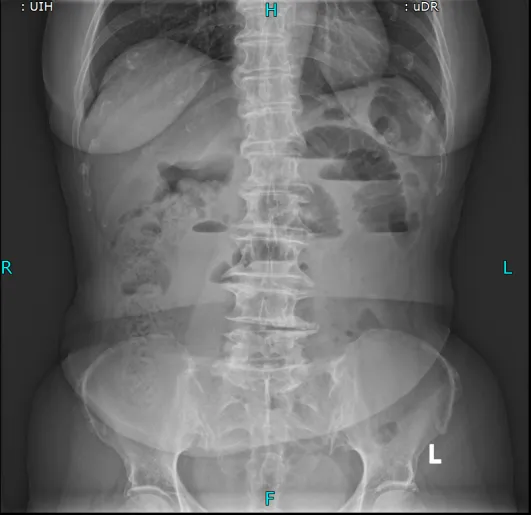

from clipboard术前立位腹平片

主任医师叶晋生结合病历和CT检查结果,明确诊断:低位小肠梗阻,且王奶奶有两次腹部手术史,肠粘连概率极高,肠管随时可能因过度扩张穿孔,需要先减压再评估。